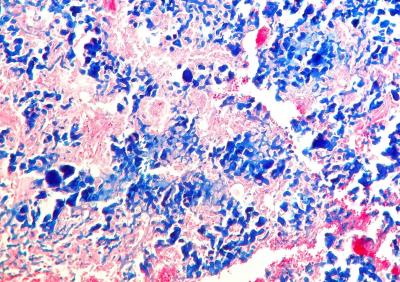

Este estudio retrospectivo fue encaminado por Celic Berenice Montoya, estudiante de especialidad del Departamento de Patología de la Facultad de Veterinaria de la prestigiosa UNAM de México, durante su rotación en Noah's Path en 2017. En el mismo, publicado recientemente en la Revista de Clínica Veterinaria de Pequeños Animales de AVEPA, se describen 6 casos de condrosarcoma en cobayas con predilección por huesos planos y, en 3 de los pacientes, metástasis. Los condrosarcomas se observan en cobayas con mayor frecuencia que en el resto de mamíferos exóticos, en los que son muy raros.